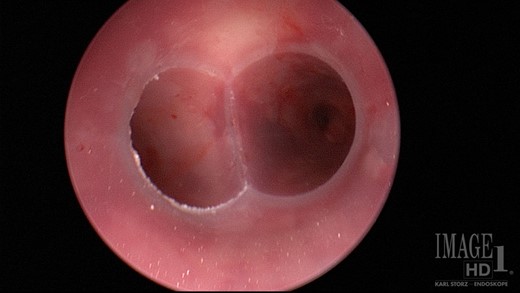

The patient was a 66-year-old white female with history of Histoplasmosis capsulatum infection and diabetes who presented as an outpatient with hemoptysis for 6 weeks. The patient was a lifelong non-smoker. A computer tomography (CT) scan of the chest revealed a calcified subcarinal lymph node along with an obstructing endobronchial lesion on the medial wall of the right mainstem bronchus (Fig. 1A). A rigid bronchoscopy was performed revealing an endobronchial mass causing a 50% obstruction of the right mainstem bronchus (Fig. 1B). The cryotherapy probe was used for mass excision and a full mediastinal staging was performed using endobronchial ultrasound (EBUS) bronchoscopy. The right mainstem bronchus was recanalized with return to 100% patency. Histology from the mass revealed an inflammatory polyp. The etiology of the inflammatory polyp was presumed to arise from inflammation stemming from the calcified station 7 lymph node abutting the medial wall of the right mainstem bronchus.

(A) Calcified subcarinal lymph node. (B) Obstructing endobronchial lesion on the medial wall of the right mainstem bronchus.